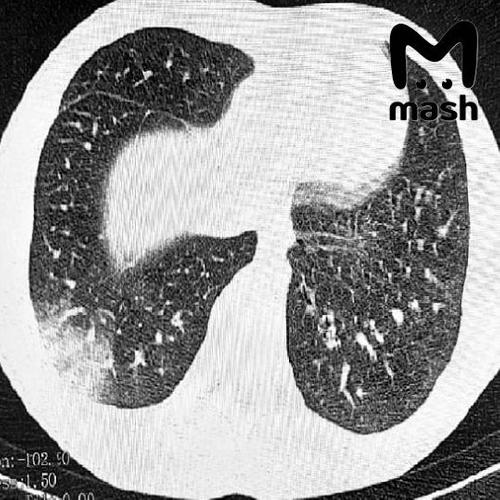

Троих зумеров экстренно доставили в реанимацию Ростовской области с попкорновой болезнью лёгких — которая развилась из-за постоянного курения вейпов

У 16-летнего пациента — серьёзная дыхательная недостаточность, потребовалась искусственная вентиляция лёгких. У другого — двусторонняя вейп-ассоциированная пневмония EVALI, врачи сделали операцию. Похожие случаи фиксируют и в других регионах России: первые в Москве в 2021-м, затем в Томске, где в прошлом году пострадали двое несовершеннолетних.

Врачи говорят: электронки серьёзно портят здоровье. Жидкости в дуделках содержат химические вещества, которые повреждают дыхательные пути, вызывают воспаление лёгких и приводят к проблемам с дыханием.